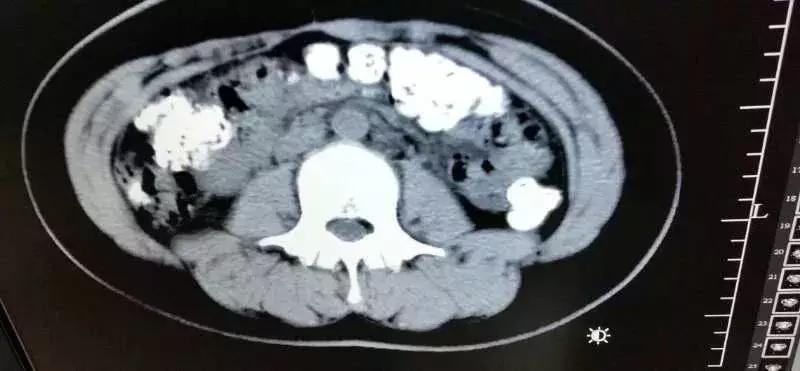

急诊科医生张楼炜对朱丽进行了初步检查,发现她肚子鼓鼓的,就让她去做了腹部CT,谁知道,拍出来的片子让张楼炜大吃一惊,患者胃部、横结肠、升结肠、降结肠、乙状结肠,一直到肛门,全是颗粒状阴影,足有百余颗。